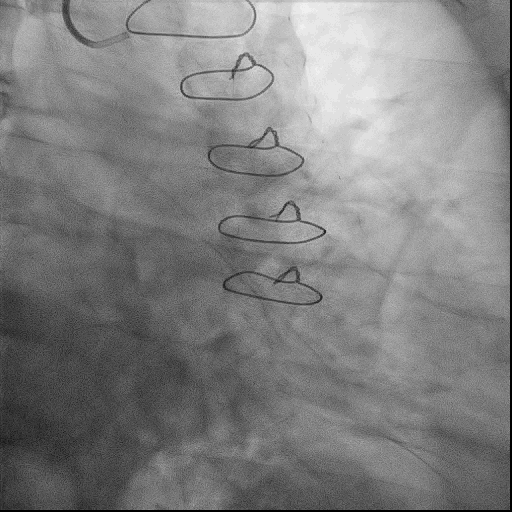

术中,球囊扩张RCA中远段后出现夹层,使用球囊压迫后复查造影TIMI血流3级,故结束手术。

术后小结: